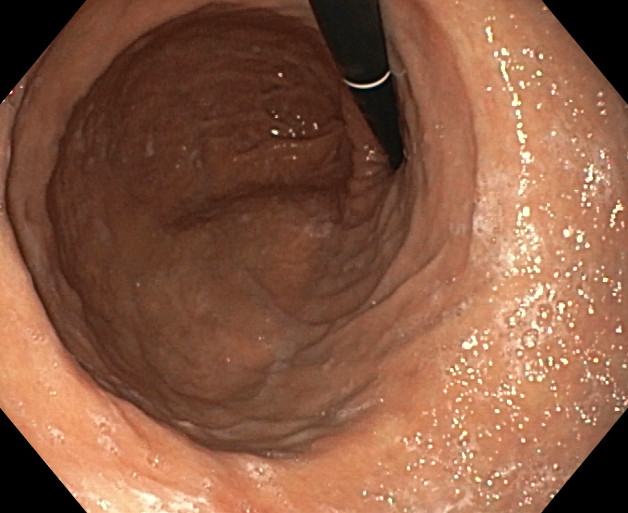

La endomanga es una técnica quirúrgica (gastroplastia) mínimamente invasiva que se realiza por vía endoscópica, es decir, a través de la boca y que permite modificar de forma definitiva la forma del estómago, acortándolo e igualmente dándole un aspecto pseudo-tubular. No se realizan incisiones externas y, por tanto, no hay cicatrices. Está indicada como primera opción para pacientes con obesidad moderada (IMC entre 30 y 40), o en caso de obesidades severas (IMC superior a 40) que no desean enfrentarse a técnicas quirúrgicas de mayor envergadura (cirugía bariátrica) para reducción del peso.

El objetivo de la endomanga gástrica es reducir el estómago, limitando la capacidad de éste. Como consecuencia de ello, el paciente presenta una mayor saciedad ingiriendo una menor cantidad de alimentos y le es más fácil adaptarse a nuevos hábitos saludables duraderos.

La gastroplastia endoscópica mediante la técnica endomanga se realiza por el gastroscopia, bajo anestesia general y dura aproximadamente entre 25 y 35 minutos. Mediante la endoscopia se realizan unos 18 pliegues definitivos a lo largo de todo el cuerpo gástrico, reduciendo de manera importante su capacidad de apertura, acortándolo y estrechándolo. Gracias a esta reducción los pacientes disminuyen la sensación de hambre.